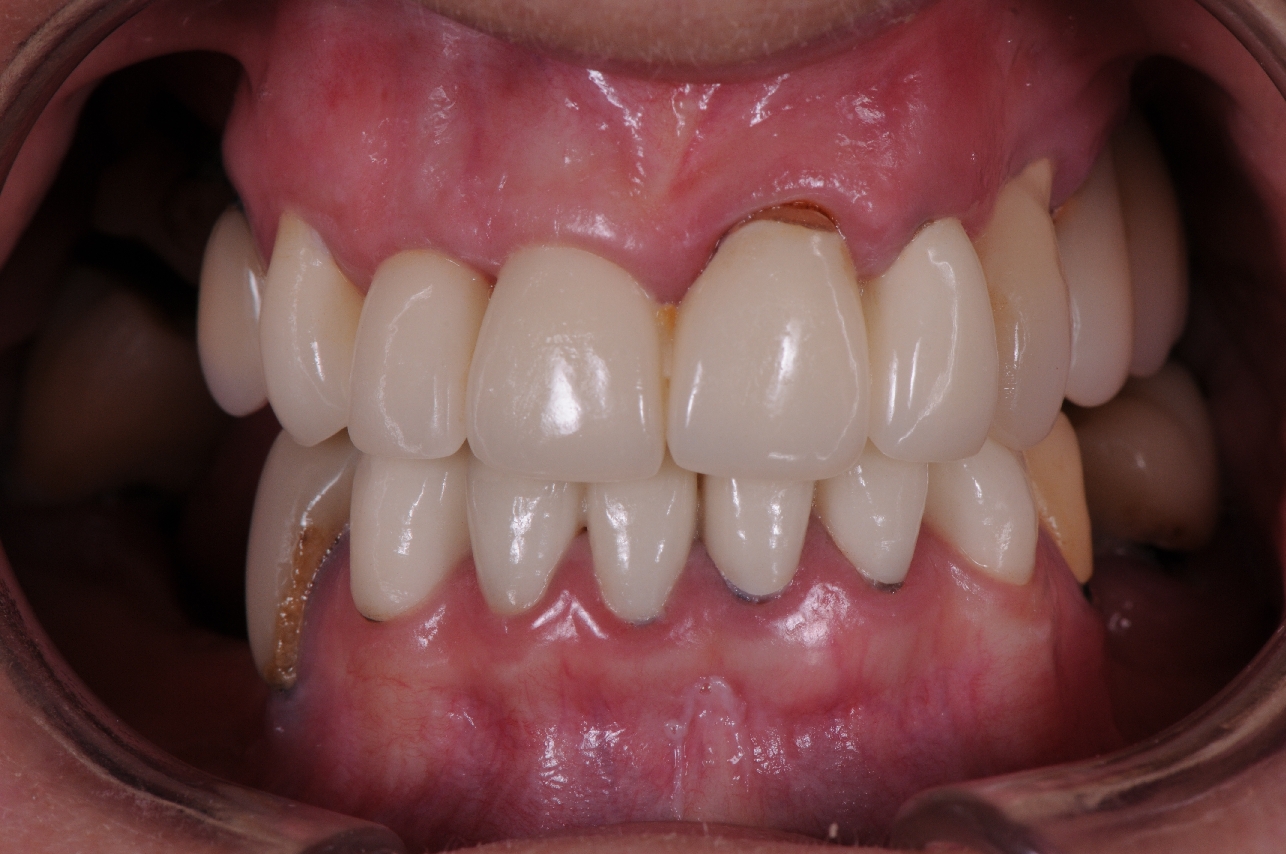

This lady presented with her teeth in very bad condition. She had decay under many of her old crowns and needed multiple root canal treatments and gum surgery in order to keep them. The long term outcome did not sound positive.

After considering all of her options, she decided that the predictability of keeping her teeth even after all of that treatment, was still going to be low. She decided to replace her teeth with implant bridges.